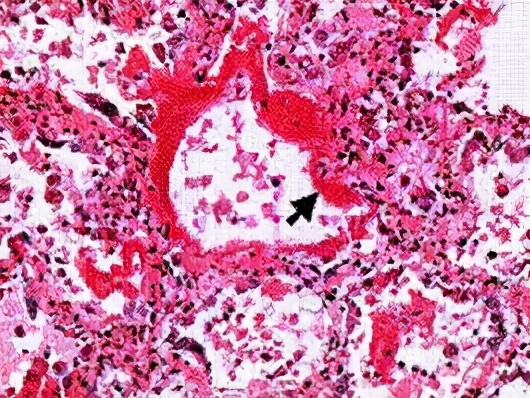

1、肾功能受损

高镁血症可见于10%-15%的住院患者,通常是肾衰竭患者。除尿液排泄外机体没有其他镁调节系统,因而血浆镁水平随肾功能下降而升高。例如,典型的终末期肾病(end-stage renal disease, ESRD)患者血浆镁浓度可达到2-3mEq/L(2.4-3.6mg/dL或1-1.5mmol/L)。透析患者的血浆镁浓度主要取决于镁的摄入量。这一点在一项横断面研究中得到了体现;这项研究纳入了完成膳食调查问卷的血液透析患者,发现估计的镁膳食摄入量与血清镁浓度之间的相关系数为0.87。

此外,镁的摄入量低至281mg/d时患者仍会发生高镁血症(定义为血清镁浓度>1.5mmol/L),而这一摄入量远低于普通人群的平均摄入量。当以常规治疗剂量给予外源性镁作为抗酸剂或轻泻药时,也可能引发重度的和有症状的高镁血症。因此,这些药物禁用于肾功能受损患者。